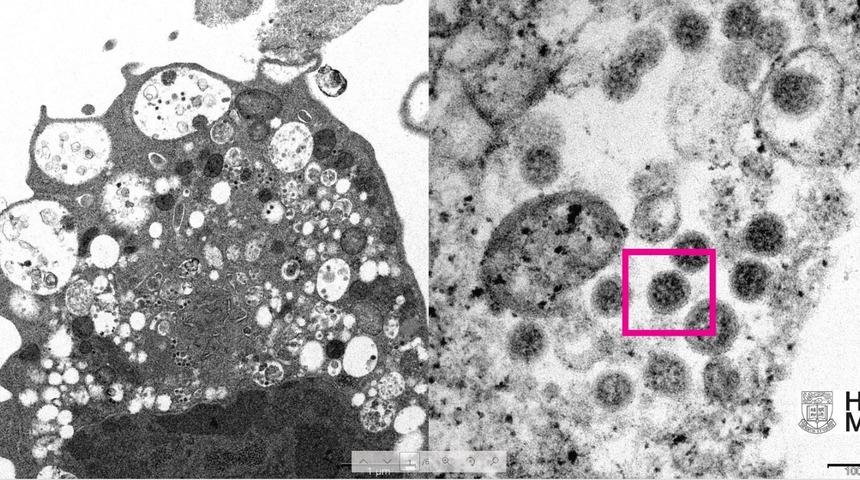

Üniversite tarafından yayınlanan fotoğrafın solunda, küçük siyah viral partiküller içeren şişmiş veziküllerle hücre hasarını gösteren, SARS-CoV-2 Omicron varyantı ile enfeksiyondan sonra bir maymun böbrek hücresinin (Vero E6) düşük büyütmeli elektron mikrografının yer aldığı ifade edildi.

Fotoğrafın sağında ise yüzeylerinde korona şekilli sivri uçlara sahip viral partikül kümelerini gösteren enfekte bir Vero E6 hücresinin yüksek büyütmeli elektron mikrografının yer aldığı belirtildi.